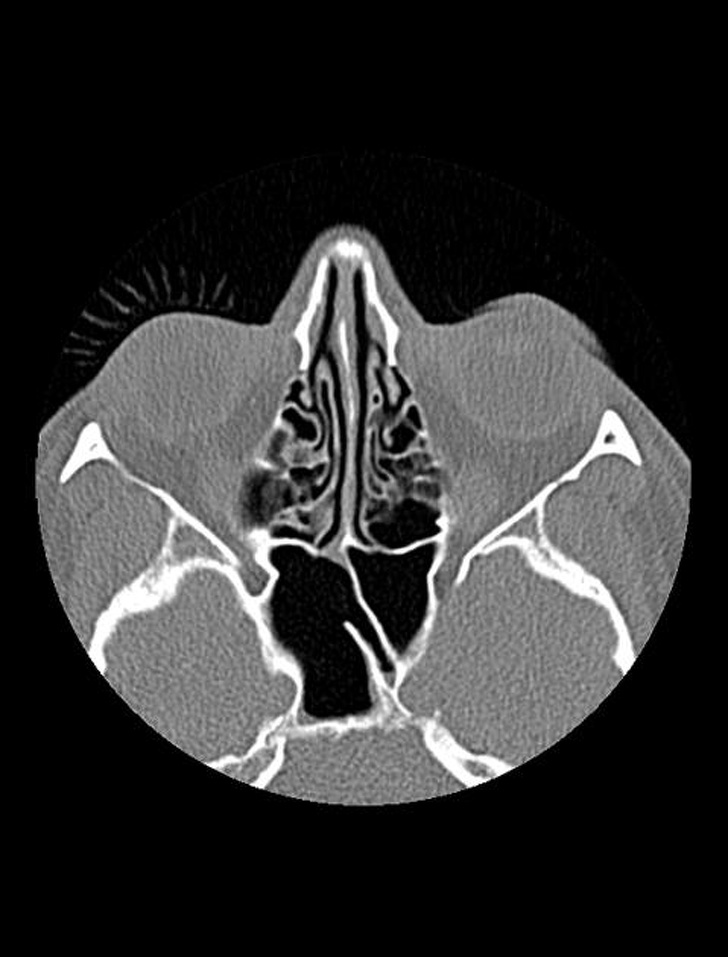

#1. The teeth of a person who is 7 (the photo on top) and a person who is 30 (the photo on the bottom)